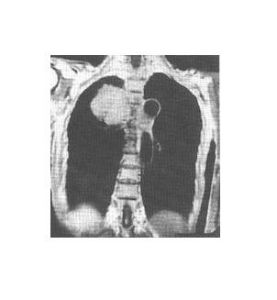

惡性淋巴瘤主要為兩側氣管旁和肺門淋巴結腫大。通常以氣管旁淋巴結腫大為主,並且多為兩側對稱性。早期可能僅表現為氣管兩旁上縱膈陰影輕度增寬。由於此類腫瘤生長迅速,發現病變時,多數明顯腫大的淋巴結均已融合成塊,使上縱膈向兩側明顯增寬,輪廓清楚而呈波浪狀,密度均勻。側位胸片見腫瘤位於中縱膈上中部,即氣管及肺門區,腫塊邊界不清楚。前縱膈胸骨後淋巴結也常被侵及,表現為緊貼於胸骨後的圓形或橢圓形帶有波浪狀向後突出的陰影。

CT掃描對顯示縱膈各組淋巴結腫大有特殊的優點,顯著優於常規X線檢查。在早期病變,縱膈輕度增寬時,CT掃描可顯示腫塊的部位和形態符合縱膈的腫大淋巴結,以及各組淋巴結受侵的範圍,對診斷很有幫助。何杰金病侵犯縱膈交非何杰金病更為多見,而且較易表現兩側病變大小不對稱。孤立的前縱膈病變,不伴有氣管旁和肺門淋巴結異常,但常伴有頸部淋巴結腫大。這類類型的淋巴瘤在X線表現上甚似胸腺瘤,在病理上常可見在腫瘤內有殘留的兇險組織。

淋巴瘤對放射治療甚為敏感,可於短期內明顯縮小以至完全消退。但對於某些何杰金病,優於合併增生的纖維住址,致放射治療後仍可保持一定體積而不完全消失。對放射治療效果好的淋巴瘤,經數年後可見鈣化影。縱膈的淋巴瘤也可侵犯膈神經、喉返神經、交感神經,出現相應的神經麻痹症狀,但一般不如轉移性淋巴結易發和顯著。

侵犯心包產生心包積液。瘤住址可經肺門沿支氣管周圍的間質向肺門侵潤,形成自肺門向肺野呈放射狀的侵潤性條狀影及細小結節影。常侵及胸膜產生胸腔積液。胸腔積液也可因縱膈的淋巴瘤阻塞了淋巴液的引流造成。此型胸腔積液,在縱膈淋巴瘤經放射治療好轉後可自行吸收。